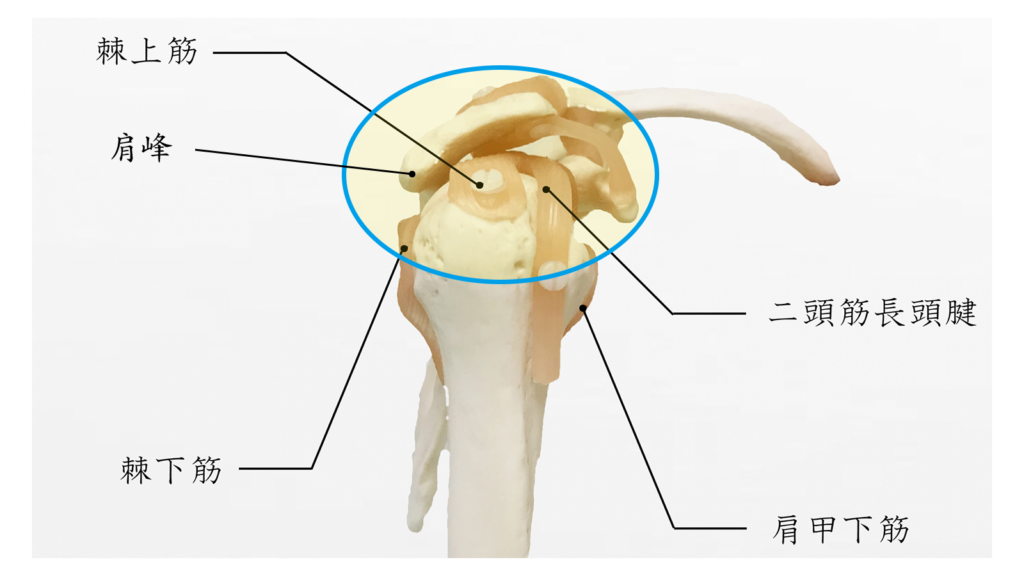

では、五十肩とは、どこが悪さをして痛みにつながっているのでしょうか?

外傷性が由来の五十肩に限ったことではありませんが、五十肩の原因は、肩の関節を構成している肩甲骨と上腕骨、そして、上腕二頭筋長頭腱、腱板を構成している棘上筋、棘下筋、大円筋、肩甲下筋が関係しています。そして、特に昔のケガの影響で、関節内にある肩峰下滑液包の癒着が最も重要とされています。

関節内にある肩峰下滑液包の癒着によって正常な働きができなくなることで、痛みや運動制限へとつながります。